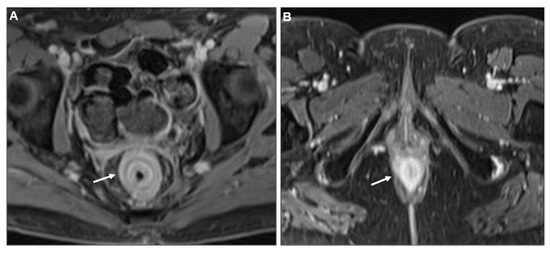

Presacral Fat Tissue and Rectovaginal Septum Infiltration and T2-Weighted Imaging (T2WI) Hypointense Extramural Tumour Component

- Lau, L.C.; Wee, B.; Wang, S.; Thian, Y.L. Metastatic breast cancer to the rectum: A case report with emphasis on MRI features. Medicine 2017, 96, e6739. [Google Scholar] [CrossRef] [PubMed]

- Rudralingam, V.; Dobson, M.J.; Pitt, M.; Stewart, D.J.; Hearn, A.; Susnerwala, S. MR imaging of linitis plastica of the rectum. AJR Am. J. Roentgenol. 2003, 181, 428–430. [Google Scholar] [CrossRef] [PubMed]